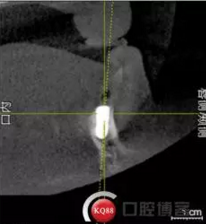

檢查:上頜無(wú)牙頜假牙穩(wěn)定性尚可,下頜3435364243殘根;33殘冠1-2度松動(dòng),其他牙齒缺失;CBCT檢查:下頜牙槽骨前牙區(qū)骨高度足,后牙區(qū)骨高度最低為8mm,骨寬度足。

1)術(shù)前檢查,拍攝臨床照片及CBCT檢查,制取活動(dòng)義齒參考模型,指導(dǎo)后期最終修復(fù)的牙齒排列

2)術(shù)前準(zhǔn)備及手術(shù)過(guò)程,測(cè)量血壓及血糖,簽種植知情同意書(shū);嚴(yán)格遵循無(wú)菌操作,局麻下采用微創(chuàng)技術(shù)于323436分別植入osstem4.0X10,4.0X10,4.5X7; 434446分別植入osstem4.0X1O,4.0X10,4.5X7.初期穩(wěn)定性均達(dá)到了35N.CM以上;嚴(yán)密縫合,止血,種植體位點(diǎn)和方向與設(shè)計(jì)一致。